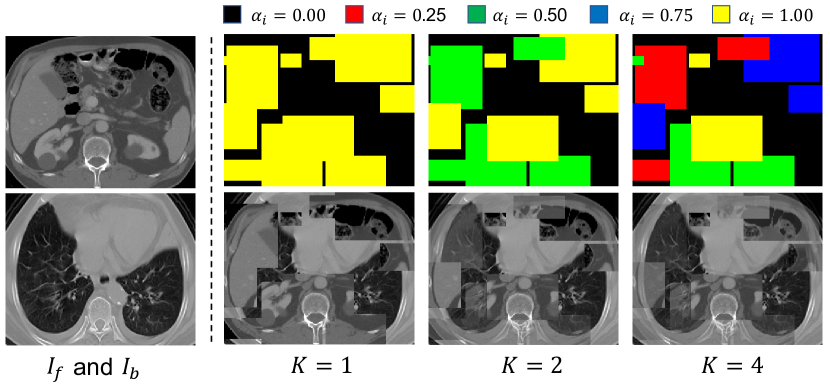

Fig. 2 shows an example of fused images with different values. In the case of = 1, the model is trained for a binary segmentation of the foreground patches from the background region. As both of the foreground and background sub-volumes are CT scans with similar intensity distributions, the model needs to find the structural discontinuity around the border of patches for the segmentation, which forces it to have a context learning ability. Note that at the center of a large patch, the structural discontinuity cannot be found based on local semantics, and the model needs to be aware of the global context to successfully recognize the category. When , there are more types of foreground patches with soft fusion coefficients, and the model needs a higher contextual semantics recognition ability for the segmentation task. Note that the foreground patches are randomly and sequentially generated at various scales and aspect ratios, and the region for each class can have irregular shapes due to overlapping of the sequential patches. Therefore, the model is encouraged to learn semantics at multiple scales in our pretext task, which is highly transferable to the downstream segmentation task for objects at various scales.